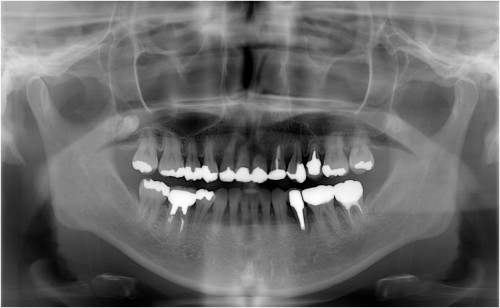

術 前

事故により左上34脱落→インプラント埋入

同拡大像

埋入後拡大像